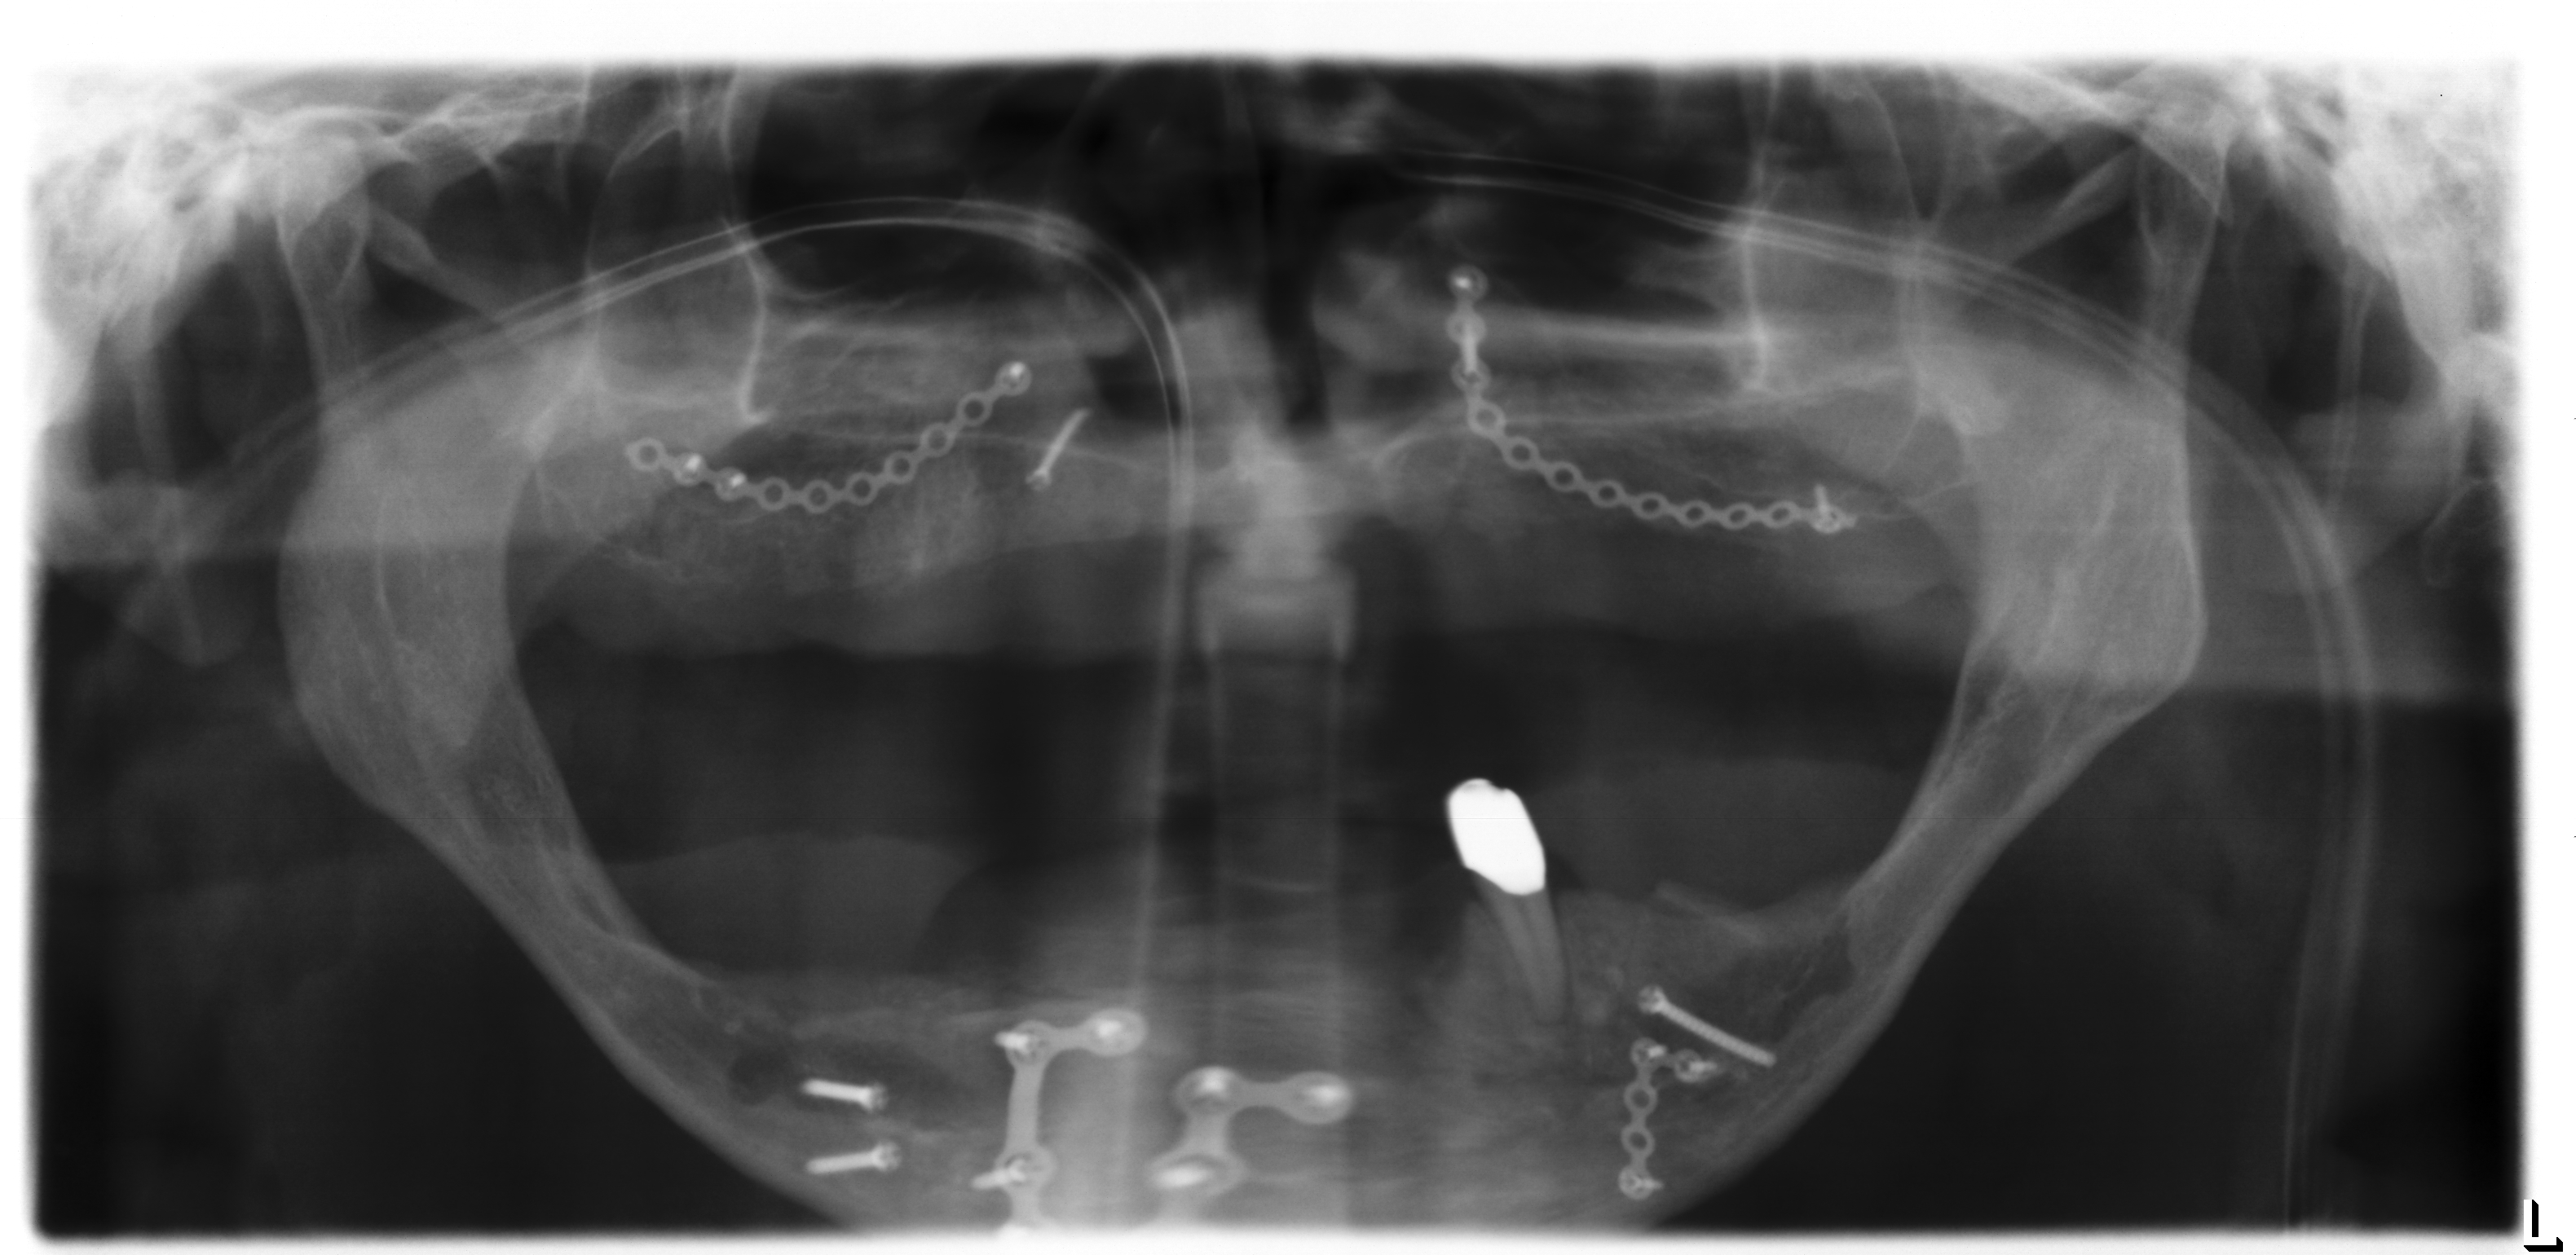

Die Ausgangssituation (Abb.1, Abb.2, Abb.3 ) zeigt einen im Oberkiefer zahnlosen (Abb.4) und im Unterkiefer mit zwei Restzähnen bezahnten Patienten (Abb.5). Der Patient leidet sehr stark unter dem fehlenden Halt der nicht mehr richtig sitzenden Oberkiefer- und Unterkieferprothesen. Diese führen für den Patienten zu einer stark verminderten Lebensqualität, da sowohl die Essensaufnahme, als auch die soziale Interaktion mit den Mitmenschen stark beeinträchtigt ist. Aufgrund des stark zurückgegangenen Knochenniveaus und dem damit verbundenen schlechten Prothesenlager, ist eine wirkliche Verbesserung der Gesamtsituation nur über zusätzliche Befestigung der Prothesen über im Knochen fixierte Zahnimplantate denkbar. Aufgrund des starken Knochenrückgangs sowohl im Ober- als auch im Unterkiefer, ist das Einbringen von Titan-Zahnimplantaten zur Stabilisierung der Prothesen nicht ohne aufwändigen Knochenaufbau möglich. Hierzu ist der Knochen den man innerhalb der Mundhöhle gewinnen kann nicht ausreichend und so bietet sich die Knochenentnahme im Bereich des Beckenkamms an.

Für derart komplexe Fälle ist das interdisziplinäre Zentrum für Zahnärztliche Implantologie der Ansprechpartner: Der Patient wird in einer interdisziplinären Sprechstunde vorgestellt und die Planung des Patienten in dem interdisziplinär geleiteten Implanatboard erstellt. Anschließend erfolgt der Knochenaufbau in ITN. Dabei werden die angelagerten Knochenstücke über sogenannte Osteosyntheseplatten in den Bereichen fixiert, an denen später die Implantate gesetzt werden sollen (Abb.6). Zeitgleich erfolgte im Unterkieferbereich eine Nervverlagerung des Unterkiefernervs und im Oberkiefer eine Knochenaufbau im Bereich der Kieferhöhlen (sogenannter „Sinuslift“) (Abb.7). Nur durch diese ausgedehnten Augmentationsmaßnahmen ist ein späteres Einbringen der Implantate sinnvoll möglich. Vier Monate später erfolgt die Entfernung der Osteosyntheseplatten (Abb.8) in Kombination mit dem Setzen der Implantate (Abb.9). Die genaue Position der Implantate wird dabei über eine individuell hergestellte Schablone (sogenannte Bohrschablone) festgelegt (Abb.10).